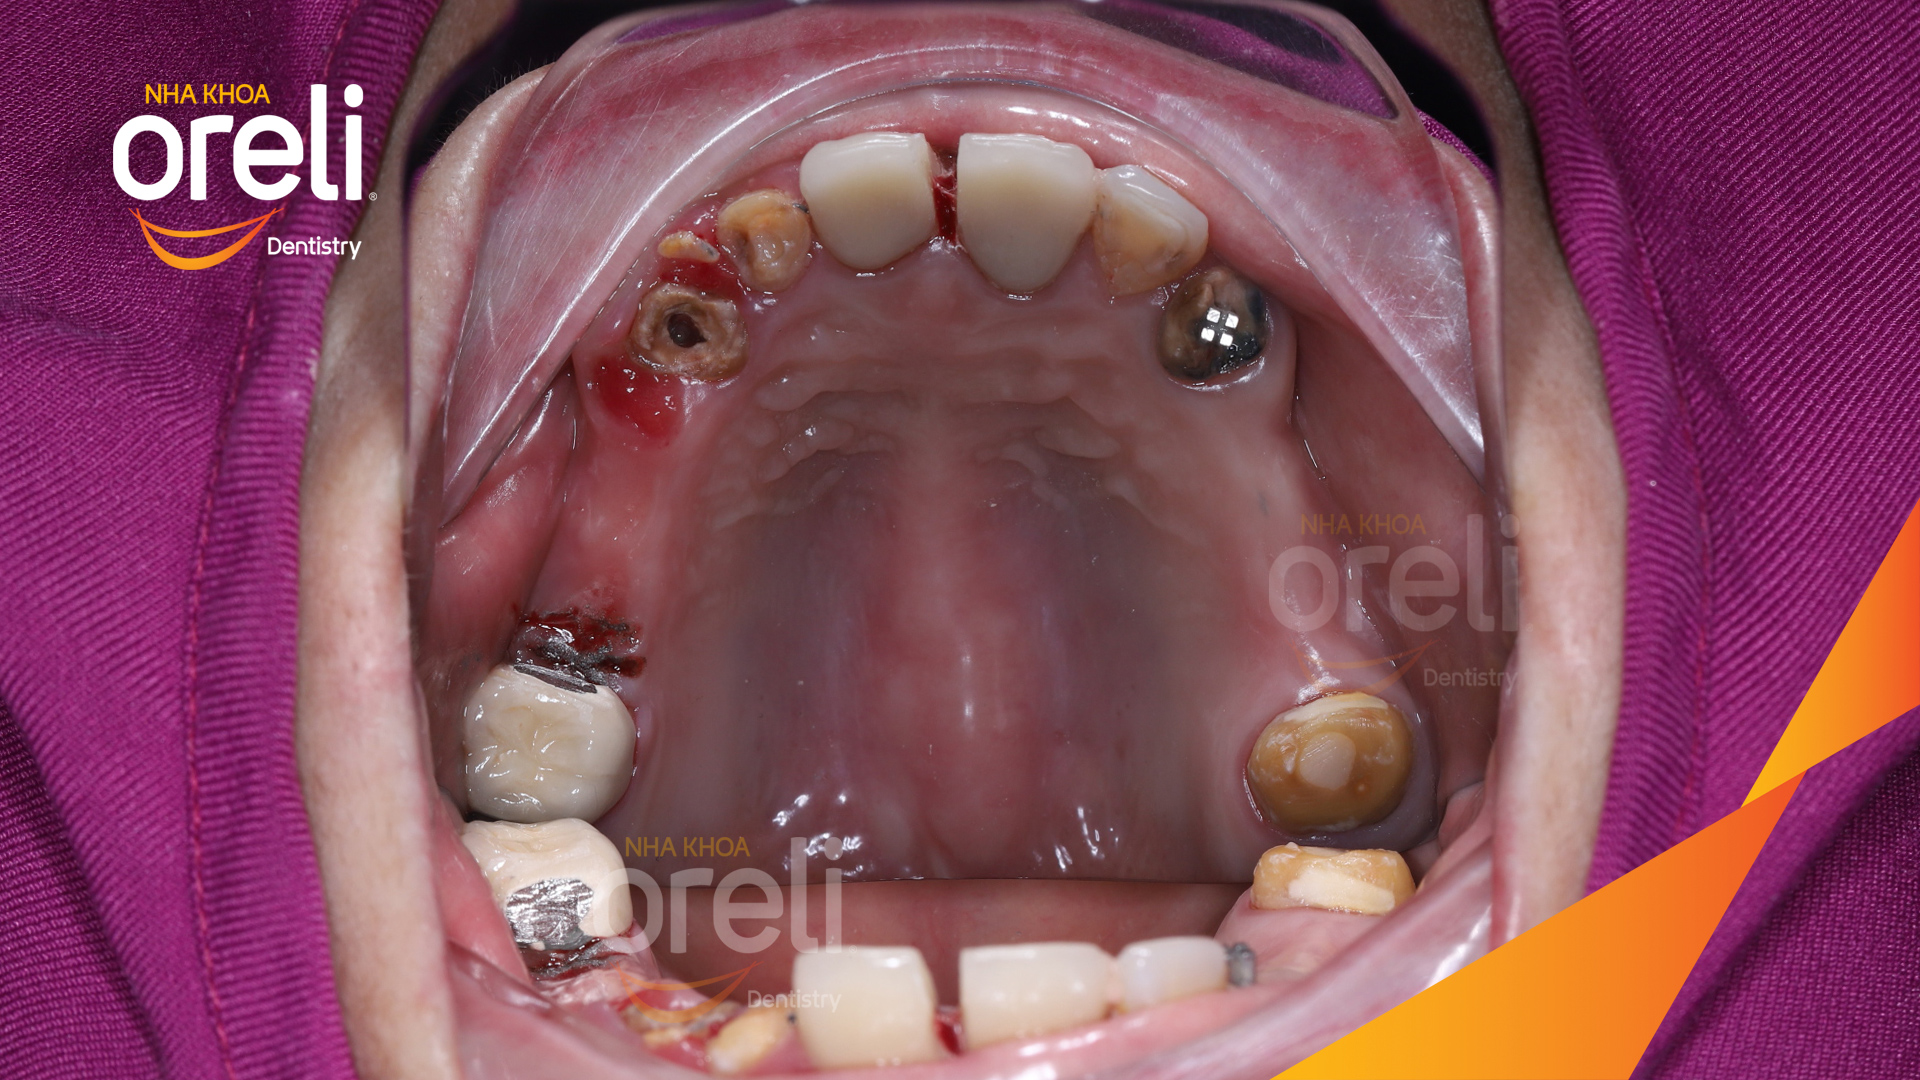

Tình trạng: Cầu răng sứ hàm trên lâu ngày gãy, viêm nướu, chân răng lung lay

Giải pháp: Cắt cầu răng sứ, nhổ răng, trồng răng implant

Hình ảnh thực tế